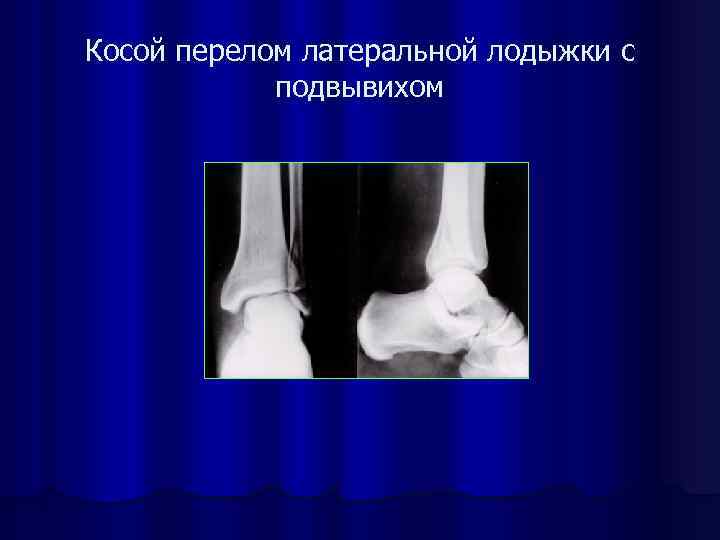

Косой перелом латеральной лодыжки с подвывихом